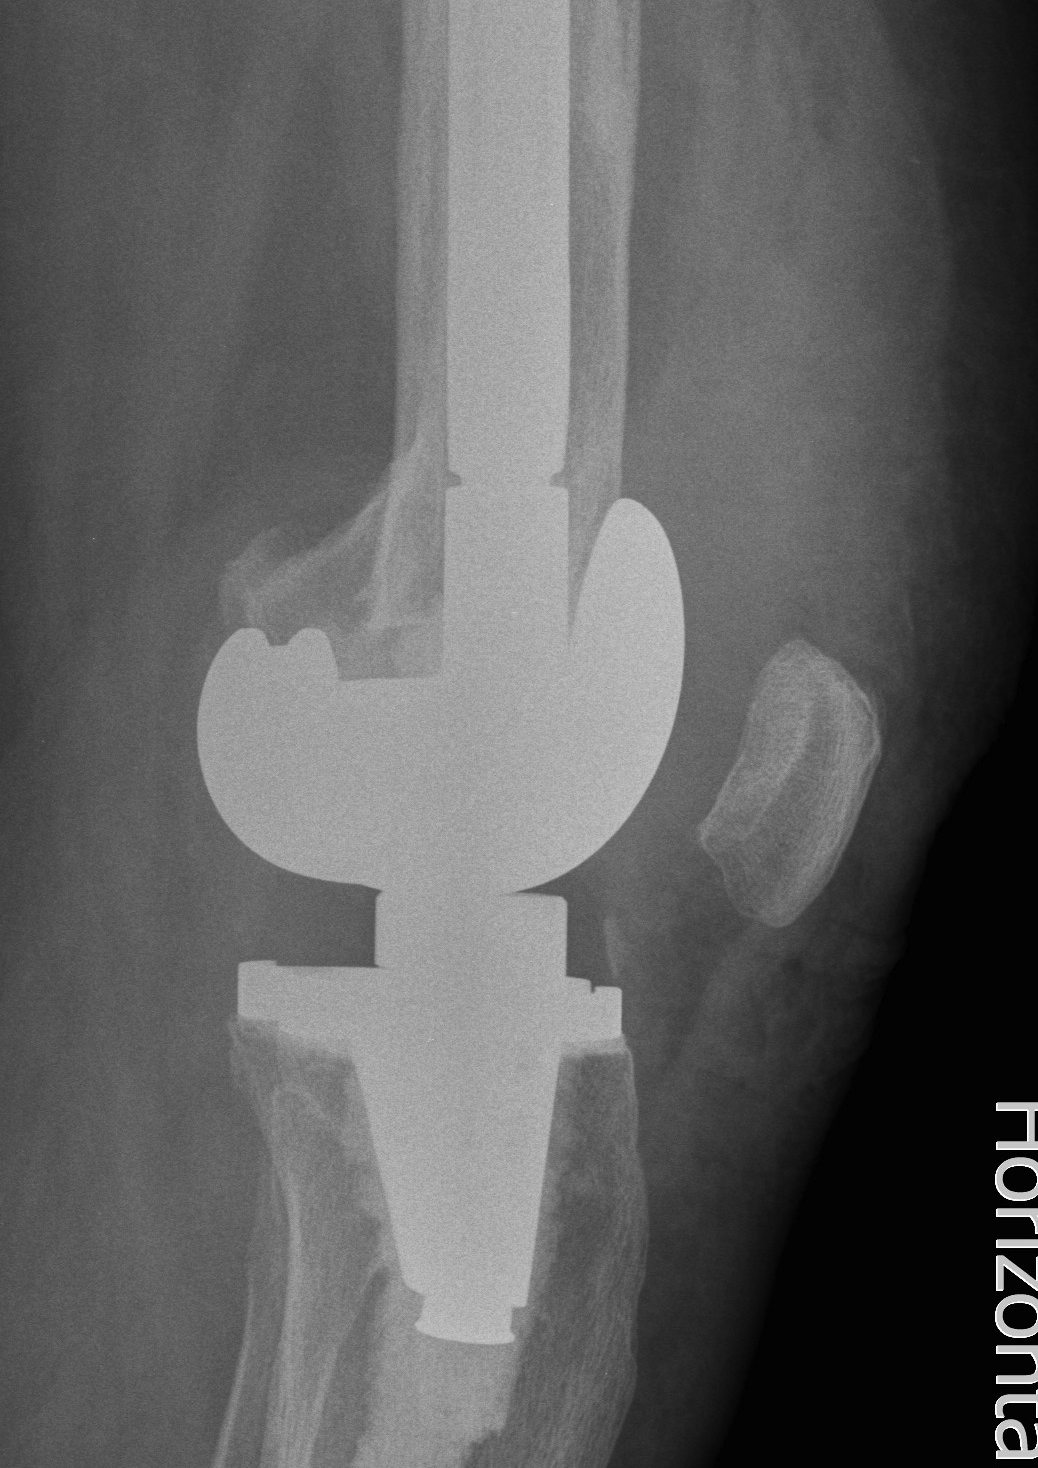

- 184 cemented revision TKR with press fit stems

- significant bone loss

10. Loosening